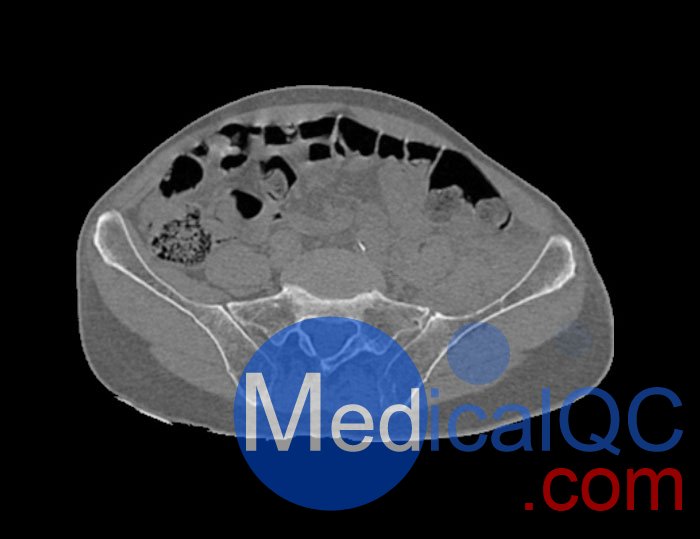

WEK54-01股骨頸骨折骨盆模型,WEK54-01骨盆模體模擬沒有靜脈造影劑的骨盆(天然)。它覆蓋了整個骨盆,直到第五腰椎。

左側股骨頸移位骨折。

該模型可用于 CT(包括 CBCT)和射線照相,以評估和優化成像性能和后處理應用,包括支持 AI 的應用。它也適用于培訓目的。

WEK54-01股骨頸骨折骨盆模型,WEK54-01骨盆模體提供了對軟組織和骨組織的詳細而逼真的模擬。空隙中填充著約-160HU的纖維素-聚合物復合材料。

骨骼和軟組織的逼真模擬。

WEK54-01股骨頸骨折骨盆模型,WEK54-01骨盆模體成像效果圖: